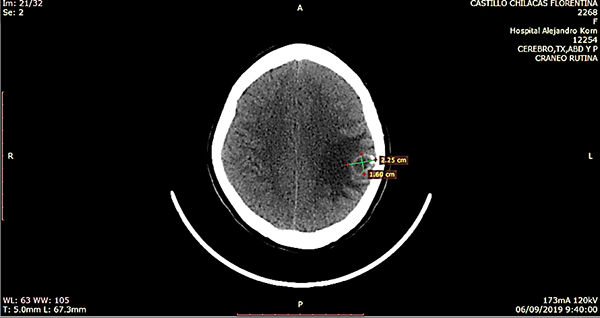

Paciente femenino de 23 años, oriunda de Bolivia, radicada desde hace 5 años en Argentina, dedicada a actividades de agricultura sin aparente nexo con cerdos, quien acude a consultorio externo por presentar cefalea intermitente de moderada intensidad, asociada a hipoestesia de mano derecha. Trae consigo una TC de cerebro simple de 30 días previos al ingreso donde se evidencia a nivel frontoparietal izquierdo lesión ocupante de espacio hipodensa con halo periférico espontáneamente densa y calcificaciones periféricas. Mide aproximadamente 22,5 mm x 16 mm y está asociado a edema de la sustancia blanca periférica, generando efecto de masa local, provocando borramiento de surcos y suturas a dicho nivel; está asociado a colapso pasivo del ventrículo lateral izquierdo (figura 1). RM con contraste visualiza imagen hipointensa en T1, hiperintensa en T2 y restricción en la difusión (figura 2).

Figura 1: TC preoperatoria. A. Corte axial, lesión hipodensa fronto parietal izquierda con halo periférico espontáneamente densa y calcificaciones periféricas, de 22,5 mm x 16 mm con gran edema periférico. B. Corte coronal, visualiza colapso pasivo del ventrículo lateral homolateral a lesión y calcificación periférica del quiste. C. Corte sagital, Lesión subcortical.